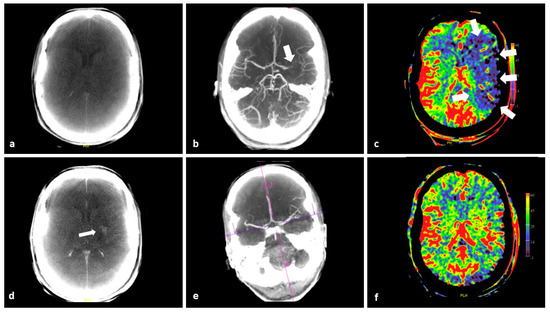

- Ava, L.; Berkefeld, J.; Lauer, A.; Seiler, A.; Pfeilschifter, W.; Müller-Eschner, M.; You, S.-J.; Weidauer, S.; Pilatus, U.; Wagner, M. Predictive Value of Pooled Cerebral Blood Volume Mapping for Final Infarct Volume in Patients with Major Artery Occlusions. A Retrospective Analysis. Clin. Neuroradiol. 2017, 27, 435–442. [Google Scholar] [CrossRef]

- Mueller, A.; Wagner, M.; Hattingen, E.; Seiler, A.; You, S.-J.; Samp, P.; Singer, O.C. Flat Panel Computed Tomography Pooled Blood Volume and Infarct Prediction in Endovascular Stroke Treatment. Stroke 2019, 50, 3274–3276. [Google Scholar] [CrossRef] [PubMed]

- Potreck, A.; Falbesaner, A.; Seker, F.; Weyland, C.S.; Mundiyanapurath, S.; Heiland, S.; Bendszus, M.; Pfaff, J.A. Accuracy and reliability of PBV ASPECTS, CBV ASPECTS and NCCT ASPECTS in acute ischaemic stroke: A matched-pair analysis. Neuroradiol. J. 2021, 34, 585–592. [Google Scholar] [CrossRef] [PubMed]